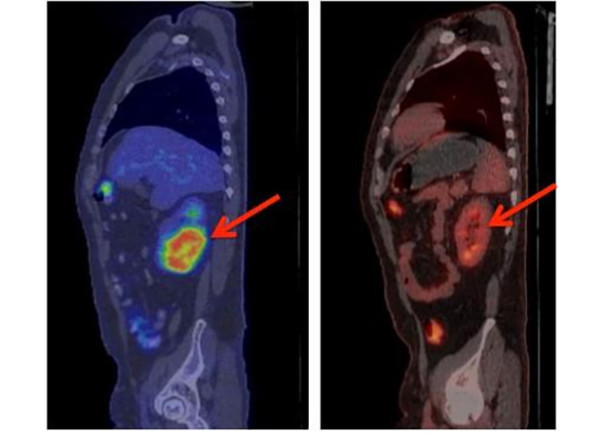

В борьбе с раком наметился прогресс, о котором проинформировали учёные. Перепрограммирование клеток в процессе опыта у нескольких десятков пациентов были взяты иммунные клетки — так называемые Т-киллеры.

В исследовании принимали участие пациенты, которым, по предположениям докторов, оставалось жить не больше полугода.

Ученые из соедененных штатов объявили о создании революционного метода лечения рака при помощи Т — клеток. «Они не только лишь запускают реакцию иммунитета на опухоль, однако и создают постоянную защиту от рака, в случае, если он появится снова», — отмечает онколог Стэнли Ридделл. Относительно недавно они исправили протокол по CAR Т-лимфоцитам, чтобы увеличить их эффективность и уменьшить побочные эффекты, среди которых может быть неврологический синдром, синдром выброса цитокинов, жар и небольшое кровяное давление.

На текущий момент ведутся дополнительные эксперименты и исследования для усовершенствования метода. Применение иммунных клеток позволило добиться полной ремиссии у 18 пациентов, что является крайне обнадеживающим результатом.